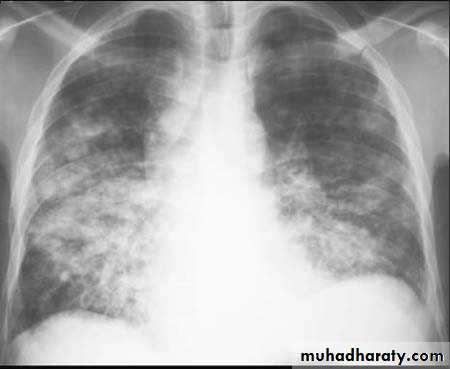

Multi-focal consolidation

Multiple areas of opacity seen throughout the lung most often is due to bronchopneumonia, starting from bronchi and spreading outwards. Usually ill defined with peripheral distribution. Neoplasms such as a primary malignancy or metastasis can also cause this picture.